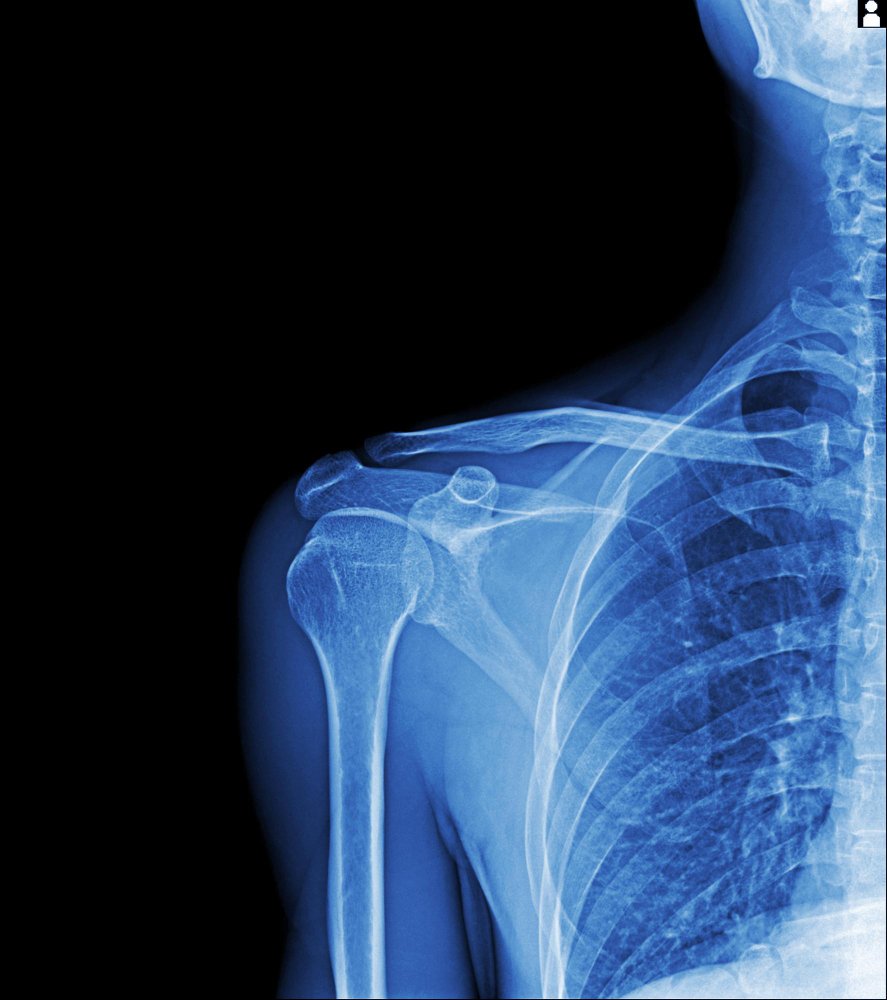

IRM de l’épaule Kenitra : à qui s’adresse cet examen et dans quels cas le prescrire

- Douleurs chroniques, limitation fonctionnelle ou instabilités après traumatisme récent ou ancien.

- Suspicion de déchirure de la coiffe des rotateurs, tendinopathies, bursites et conflits sous‑acromiaux.

La radiographie reste la première intention pour étudier l’os et la densité osseuse. Elle dépiste calcifications et arthrose.

La technique magnétique permet visualiser finement muscles, tendons et bourses du corps. Les images renseignent sur l’œdème osseux et les lésions associées, utiles au chirurgien orthopédiste.

Notre recommandation : réaliser d’abord une radiographie si indiqué, puis un examen d’imagerie médicale ciblé si les tissus mous sont en cause. La décision se prend avec votre prescripteur et notre radiologue.